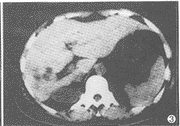

例2 女,43岁。上腹痛10天。CT扫描示肝右叶背段见不规则低密度区,边界欠清;增强后强化不明显(图3),肝脏后下缘与后胸壁间见一类圆形低密度影,边缘清(图4)。术前诊断为胆管细胞癌。术后病理:(1)肝右叶后胆囊;(2)肝右叶胆汁淤积。

图3 肝右叶背段斑片状低密度灶,强化不明显